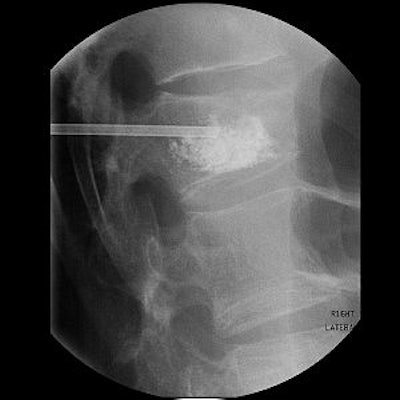

A vertebral compression fracture causing pain and spinal deformity (above). Below, a biopsy needle is guided into the fractured vertebra through a small incision in the skin. Inset shows a magnified view of the interior of the osteoporotic vertebra with the needle in place.